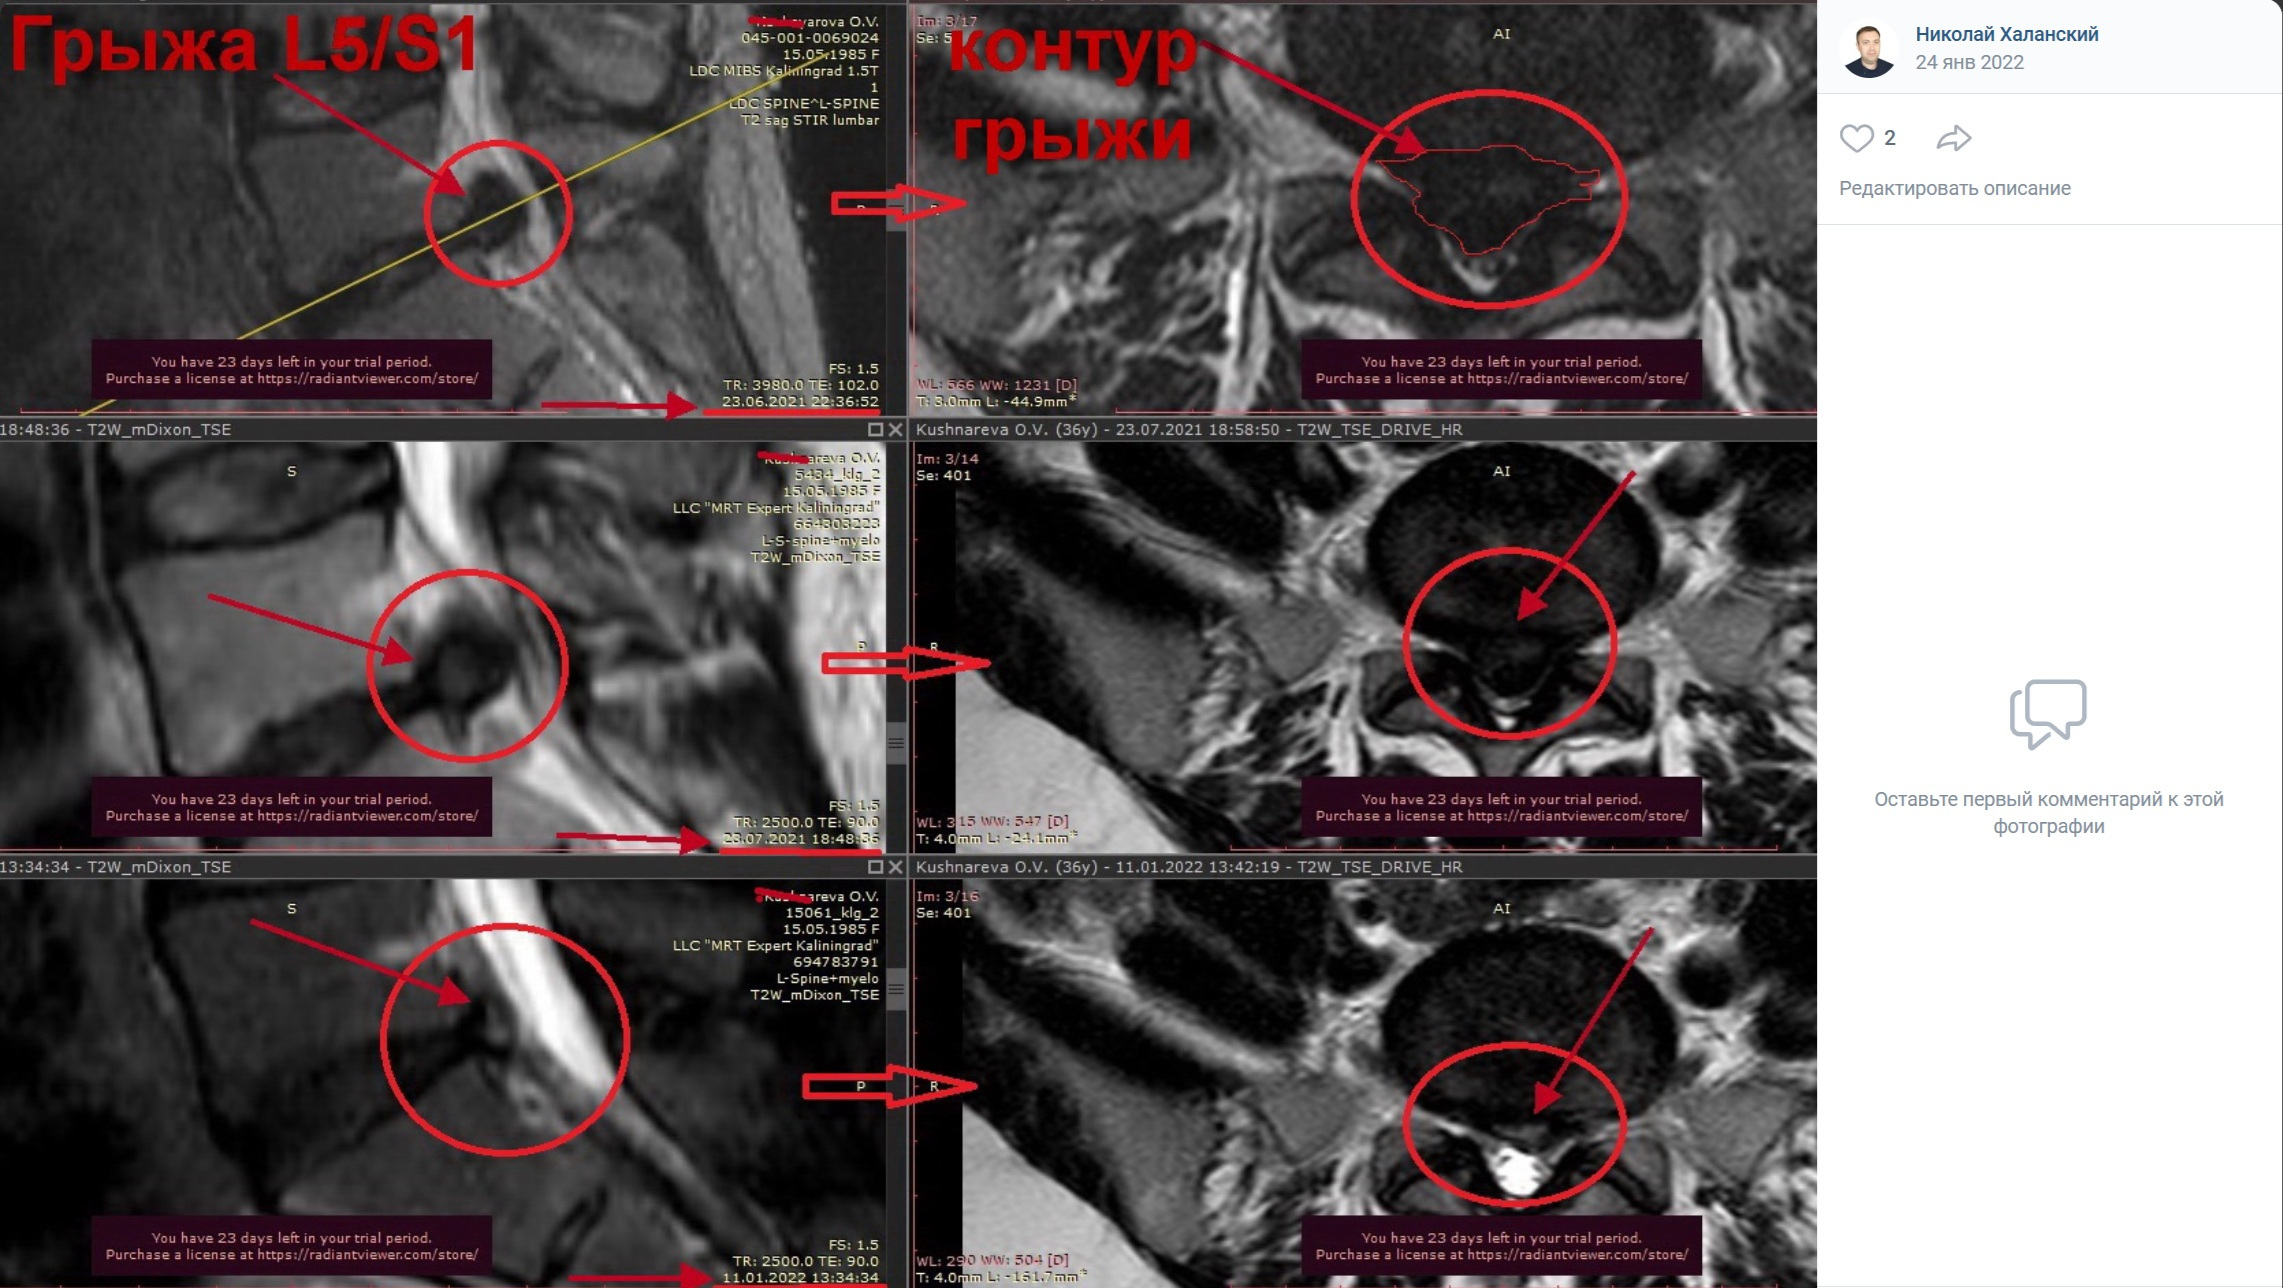

Примеры лизирования грыж

и секвестров

(Резорбция межпозвонковой грыжи)

выполненные главным врачем клиники Халанским Н.Н.